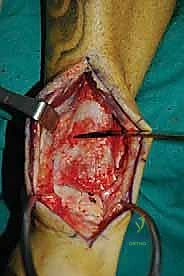

ثالثاً: الحل الجذري - إعادة بناء الطعم الخيفي الهيكلي

بالنسبة للمرضى الذين يعانون من آلام مزمنة، وتظهر صورهم آفة كبيرة الحجم، عميقة، تحتوي على تكيسات ضخمة، أو تشمل حواف التالوس (الكتف)، تصبح إعادة بناء الطعم الخيفي الهيكلي هي الحل الأمثل والذهبي.

الغوص العميق في جراحة الطعم الخيفي الهيكلي (Structural Allograft Reconstruction)

يهدف هذا الإجراء العبقري إلى استبدال الغضروف والعظم التالفين والميتين بنسيج سليم تماماً مأخوذ من متبرع متوفى (طعم خيفي - Allograft). هذا الطعم يتم تعقيمه وحفظه في بنوك الأنسجة العالمية وفقاً لأعلى المعايير الطبية الصارمة لضمان خلوه من أي أمراض معدية والحفاظ على حيوية الخلايا الغضروفية.